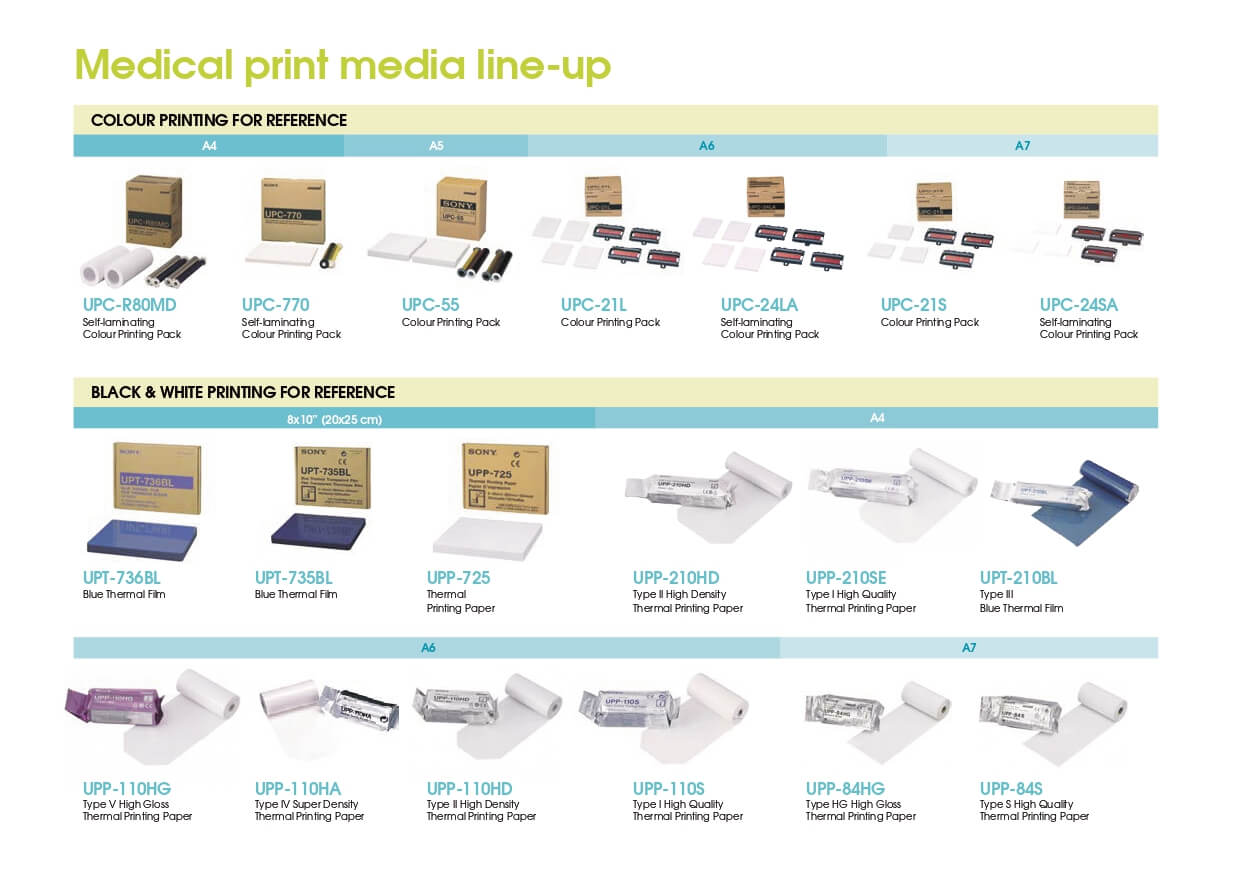

فیلم حرارتی آبی شفاف UPT-210BL

فیلم حرارتی شفاف سونی با کیفیت و وضوح عالی برای پرینترهای هیبریدی UP-991AD، UP-990AD و UP-980AD مناسب است. همچنین، فیلم حرارتی آبی شفاف UPT-210BL با ابعاد ۴۹۲×۱/۴ ۸ اینچ (۱۲۵۰۰×۲۱۰ میلیمتر) برای چاپ تصاویر با کیفیت بالا در پرینتر پزشکی UP-990AD قابل استفاده است. هر رول این فیلم برای گرفتن ۴۲ پرینت مناسب است.

| Blue Thermal Transparent Film | Type of Media |

| 210mm×12.5m | Contents |

| 210mm×12.5m (8 1/4×492inches) | Paper/Film Size |

| Approximately 42 Prints | Print Pages for One Roll |

| UP-991AD, UP-990AD, UP-980AD | Supported Printers |